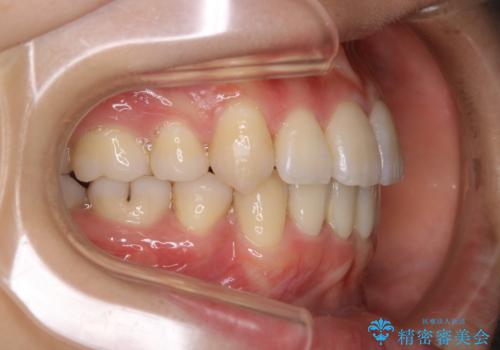

- 以前からコンプレックスだった八重歯の治療を主訴にご来院されました。

検査の結果、抜歯をすることでスペースを作って並べる方法が選択され、ワイヤー装置を用いた治療を開始することとなりました。

奥歯の上下のズレ等は軽度で、必要なスペースと抜歯により作られるスペースがほぼ等量だったため治療の単純化が計れ、大きな移動・見た目の劇的な変化に対して比較的早期での治療完了となりました。

叢生の度合いが重く、抜歯が必要なケース。八重歯の部分以外には大きな問題は認められなかったため、劇的変化が起こる治療でも比較的短期間で終了することができました。